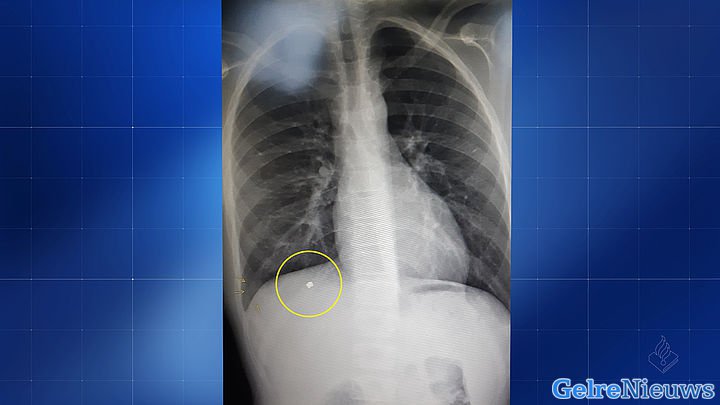

Beschoten jongen (13) moet leven met kogel in zijn lichaam Beschoten jongen (13) moet leven met kogel in zijn lichaam BARNEVELD | VIDEO ONDER HET ARTIKEL - Tijdens het spelen op een schoolplein aan de Saparua in...